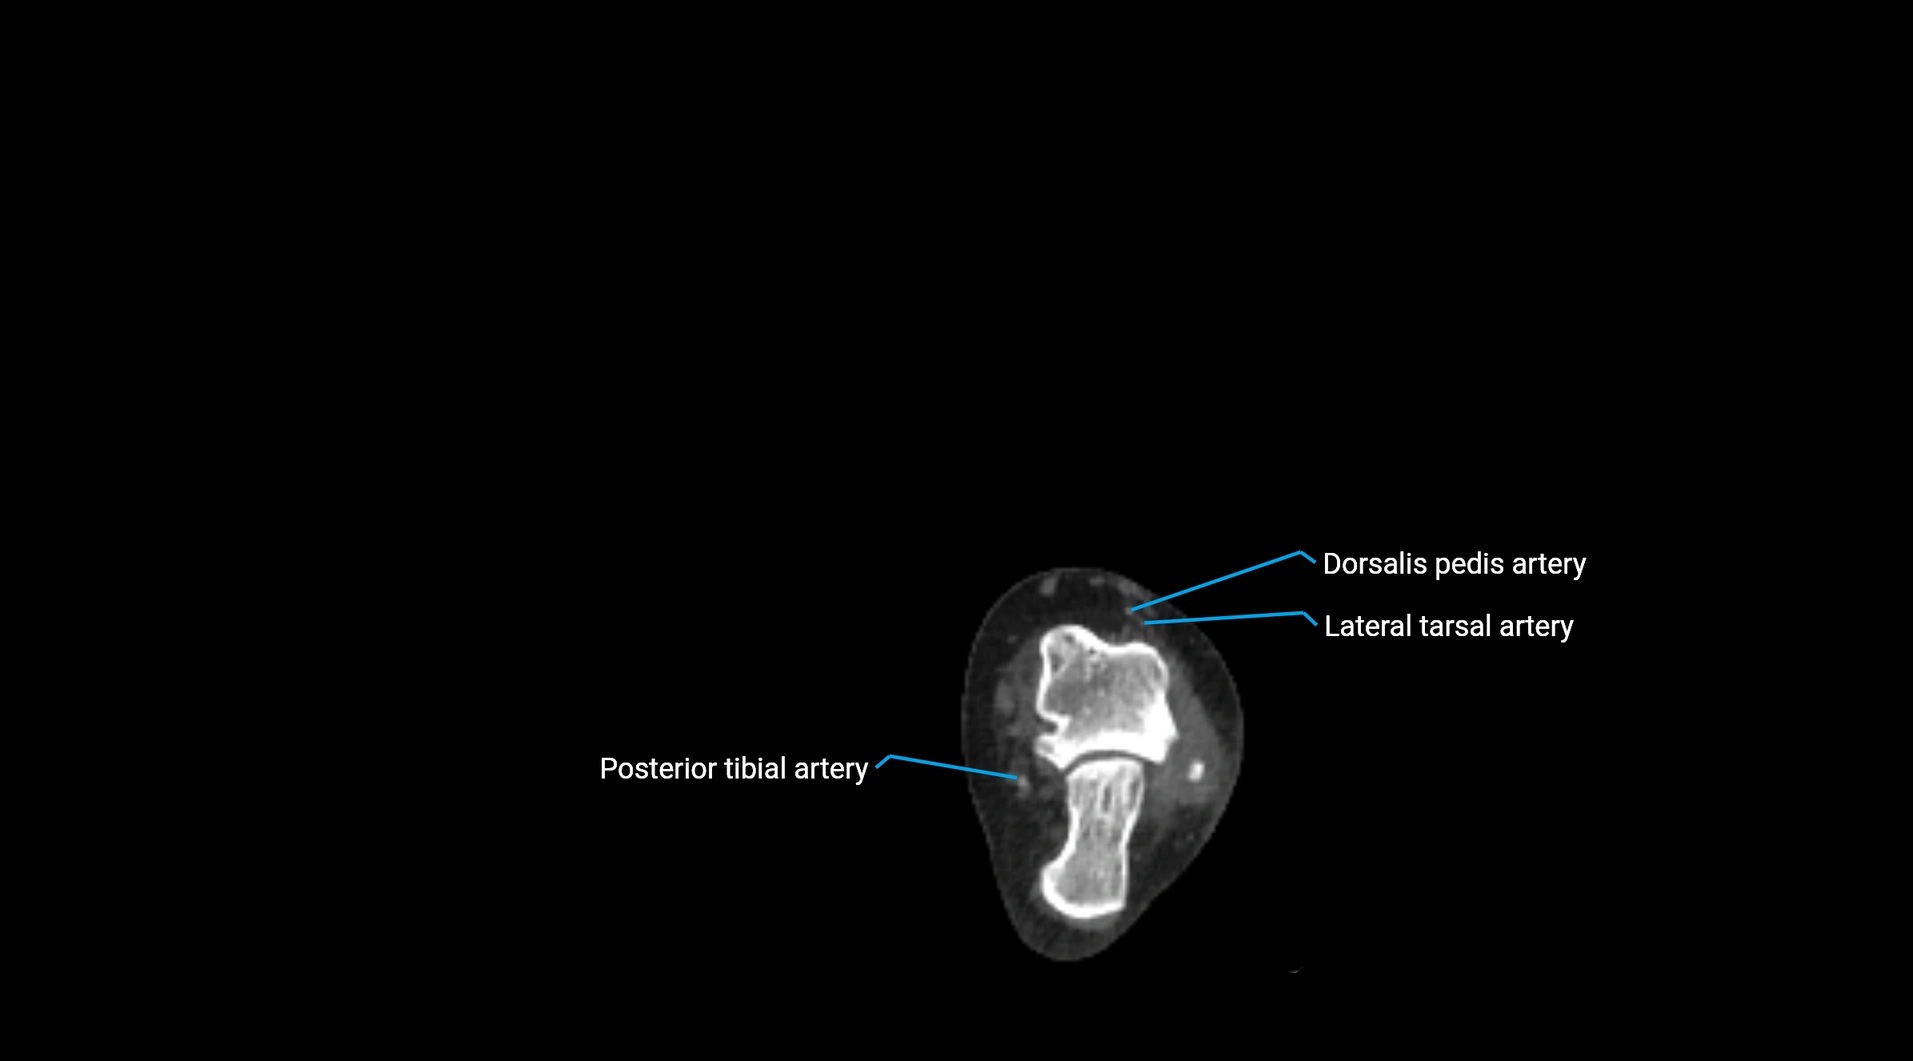

CT images

image

Contrast-enhanced CT (CTA):

• Gold standard for abdominal aortic imaging

• Provides excellent detail of lumen, wall, aneurysm, thrombus, and branch vessels

• Multiplanar and 3D reconstructions help in aneurysm measurement, stent graft planning, and dissection evaluation